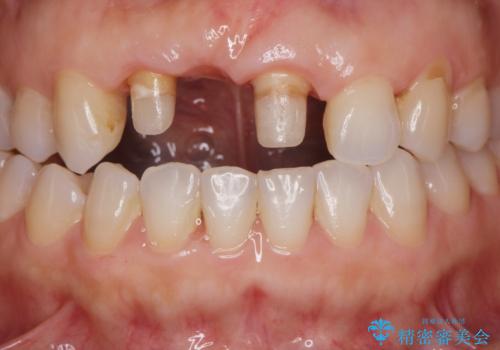

- 前歯のブリッジがすぐに外れる、歯ぐきが腫れている、見た目を良くしたい、と希望され来院されました。

現在装着されているブリッジを除去したところ、歯ぐきよりも上に存在する歯質(縁上歯質)が少なく、土台の形態の悪さや不適合などさまざまな問題があります。